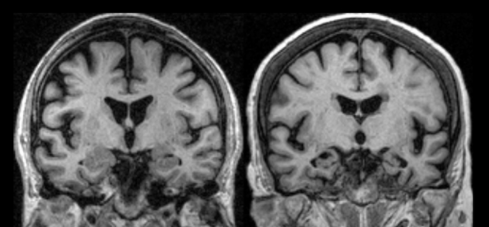

알츠하이머병은 뇌 신경세포가 서서히 죽어가는 퇴행성 신경 질환으로 이상 단백질(아밀로이드 베타 단백질, 타우 단백질)이 뇌 속에 쌓이면서 생기는 질환입니다. 정상적인 사람이 나이가 들면서 세포가 손상되어 점차 증세가 나타나기 때문에 퇴행성이라는 단어가 붙었습니다.

치매 증상을 일으킬 수 있는 신체 질환이 있는지를 혈액 검사, 소변 검사, 흉부 방사선 검사, 심전도 검사 등을 통해 검사하고, 신경 심리 검사를 통해 기억력, 판단력, 언어 능력 등의 인지 기능을 평가합니다. 또한, MRI, CT, PET 등의 뇌 영상검사를 시행하여 뇌의 구조적, 기능적 상태를 평가합니다.